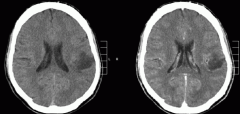

脑干胶质瘤约占全部后颅窝肿瘤的25%,较常见于7至9岁的儿童。没...

脑干神经胶质瘤是一种发生在脑干的肿瘤。它较常见于20岁以下的...